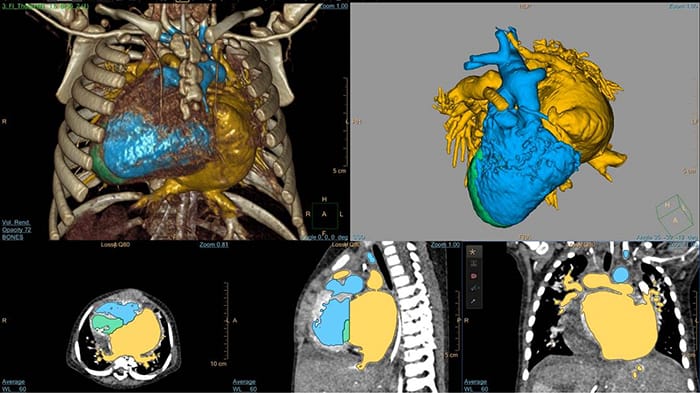

Modelowanie 3D z użyciem systemu IntelliSpace Portal

Analiza D-TGA z użyciem systemu HeartNavigator u 5-dniowego noworodka